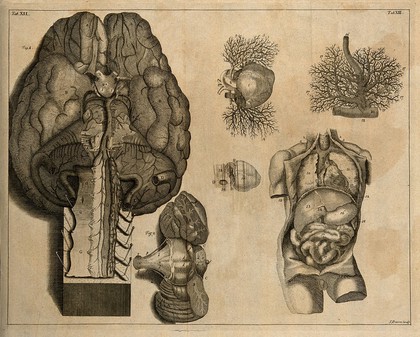

The anatomy of the brain : containing its mechanism and physiology : together with some new discoveries and corrections of ancient and modern authors upon that subject : to which is annex'd a particular account of animal functions and muscular motion : the whole illustrated with elegant sculptures after the life by H. Ridley.

Ridley, Humphrey, 1653-1708Date: 1695

The brain, after Haller and Ridley. Engraving by Prevost, 1762.

The brain, after Haller and Ridley. Engraving, 18th century.

The brain, after Haller and Ridley. Engraving by Benard, late 18th century.